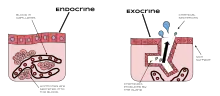

In animals, a gland is a group of cells[1] in an animal's body (and used by myrmecophyte plants to feed their ant symbiotes) that synthesizes substances (such as hormones) for release into the bloodstream (endocrine gland) or into cavities inside the body or its outer surface (exocrine gland).

Endocrine glands

Endocrine glands secrete substances that circulate through the blood stream. The glands secrete their products through basal lamina into the blood stream. Basal lamina typically can be seen as a layer around the glands to which a million, maybe more, tiny blood vessels are attached. These glands often secrete hormones which play an important role in maintaining homeostasis. The pineal gland, thymus gland, pituitary gland, thyroid gland, and the two adrenal glands are all endocrine glands.

Exocrine glands

Exocrine glands secrete their products through a duct onto an outer or inner surface of the body, such as the skin or the gastrointestinal tract. Secretion is directly onto the apical surface. The glands in this group can be divided into three groups: